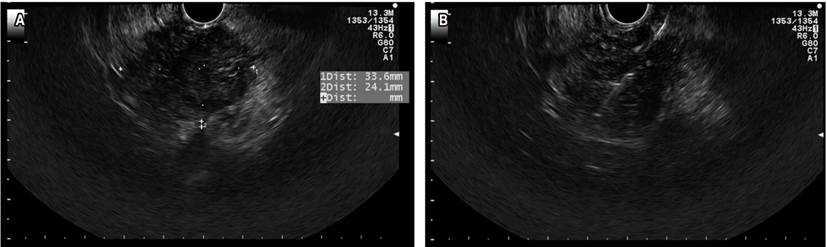

The European Society of Gastrointestinal and Abdominal Radiology (ESGAR), in its guidelines for the study of rectal neoplasms, states that EUS is the method of choice for the differentiation and staging of rectal T1 lesions (Figure 5)23. When compared to traditional endoscopy, EUS has been shown to reduce the risk of undiagnosed carcinoma in polypoid rectum lesions from 21% to 3%24. In this context, the use of EUS elastography to measure elastic properties such as tissue hardness has begun to be studied with the aim of distinguishing benign from rectal malignant polyps. In this sense, a study has reported that elastography could allow differentiating benign adenomas from invasive adenocarcinomas with a sensitivity of 96%, a specificity of 86%, and a diagnostic accuracy of 94% when compared with the pathology report25.

Rectal cancer

Proper staging of rectal cancer is crucial to determining the prognosis and the best treatment for the patient. The uT classification is proposed as a staging tool for rectal cancer to identify the T (tumor) (Table 2)26. While EUS might be superior in staging T in early lesions (T1), but its performance is inferior to that of MRI in terms of accuracy in staging T2 and larger lesions22. In this regard, a meta-analysis published in 2004 found that EUS and MRI had comparable diagnostic results in staging N (nodes) in rectal tumors, with a sensitivity and specificity of 67% and 78% and 66% and 76%, respectively27.